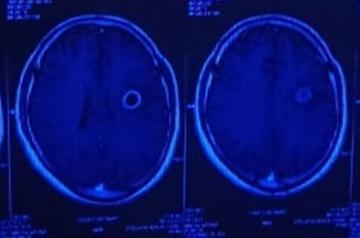

Ring enhancing lesion

It was a great relief to get an exact diagnosis and not having to treat the ailment empirically. The first MRI indicated a strong probability of a pyogenic infection which might or might not have been due to TB. The patient would have received broad-spectrum antibiotics which would not have helped him but would have affected his kidneys adversely.